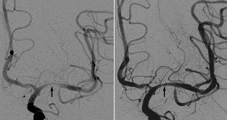

左圖箭頭所指是治療前血管嚴重狹窄處,右圖為支架放完後血管大小接近正常,遠端血流量也明顯增加。